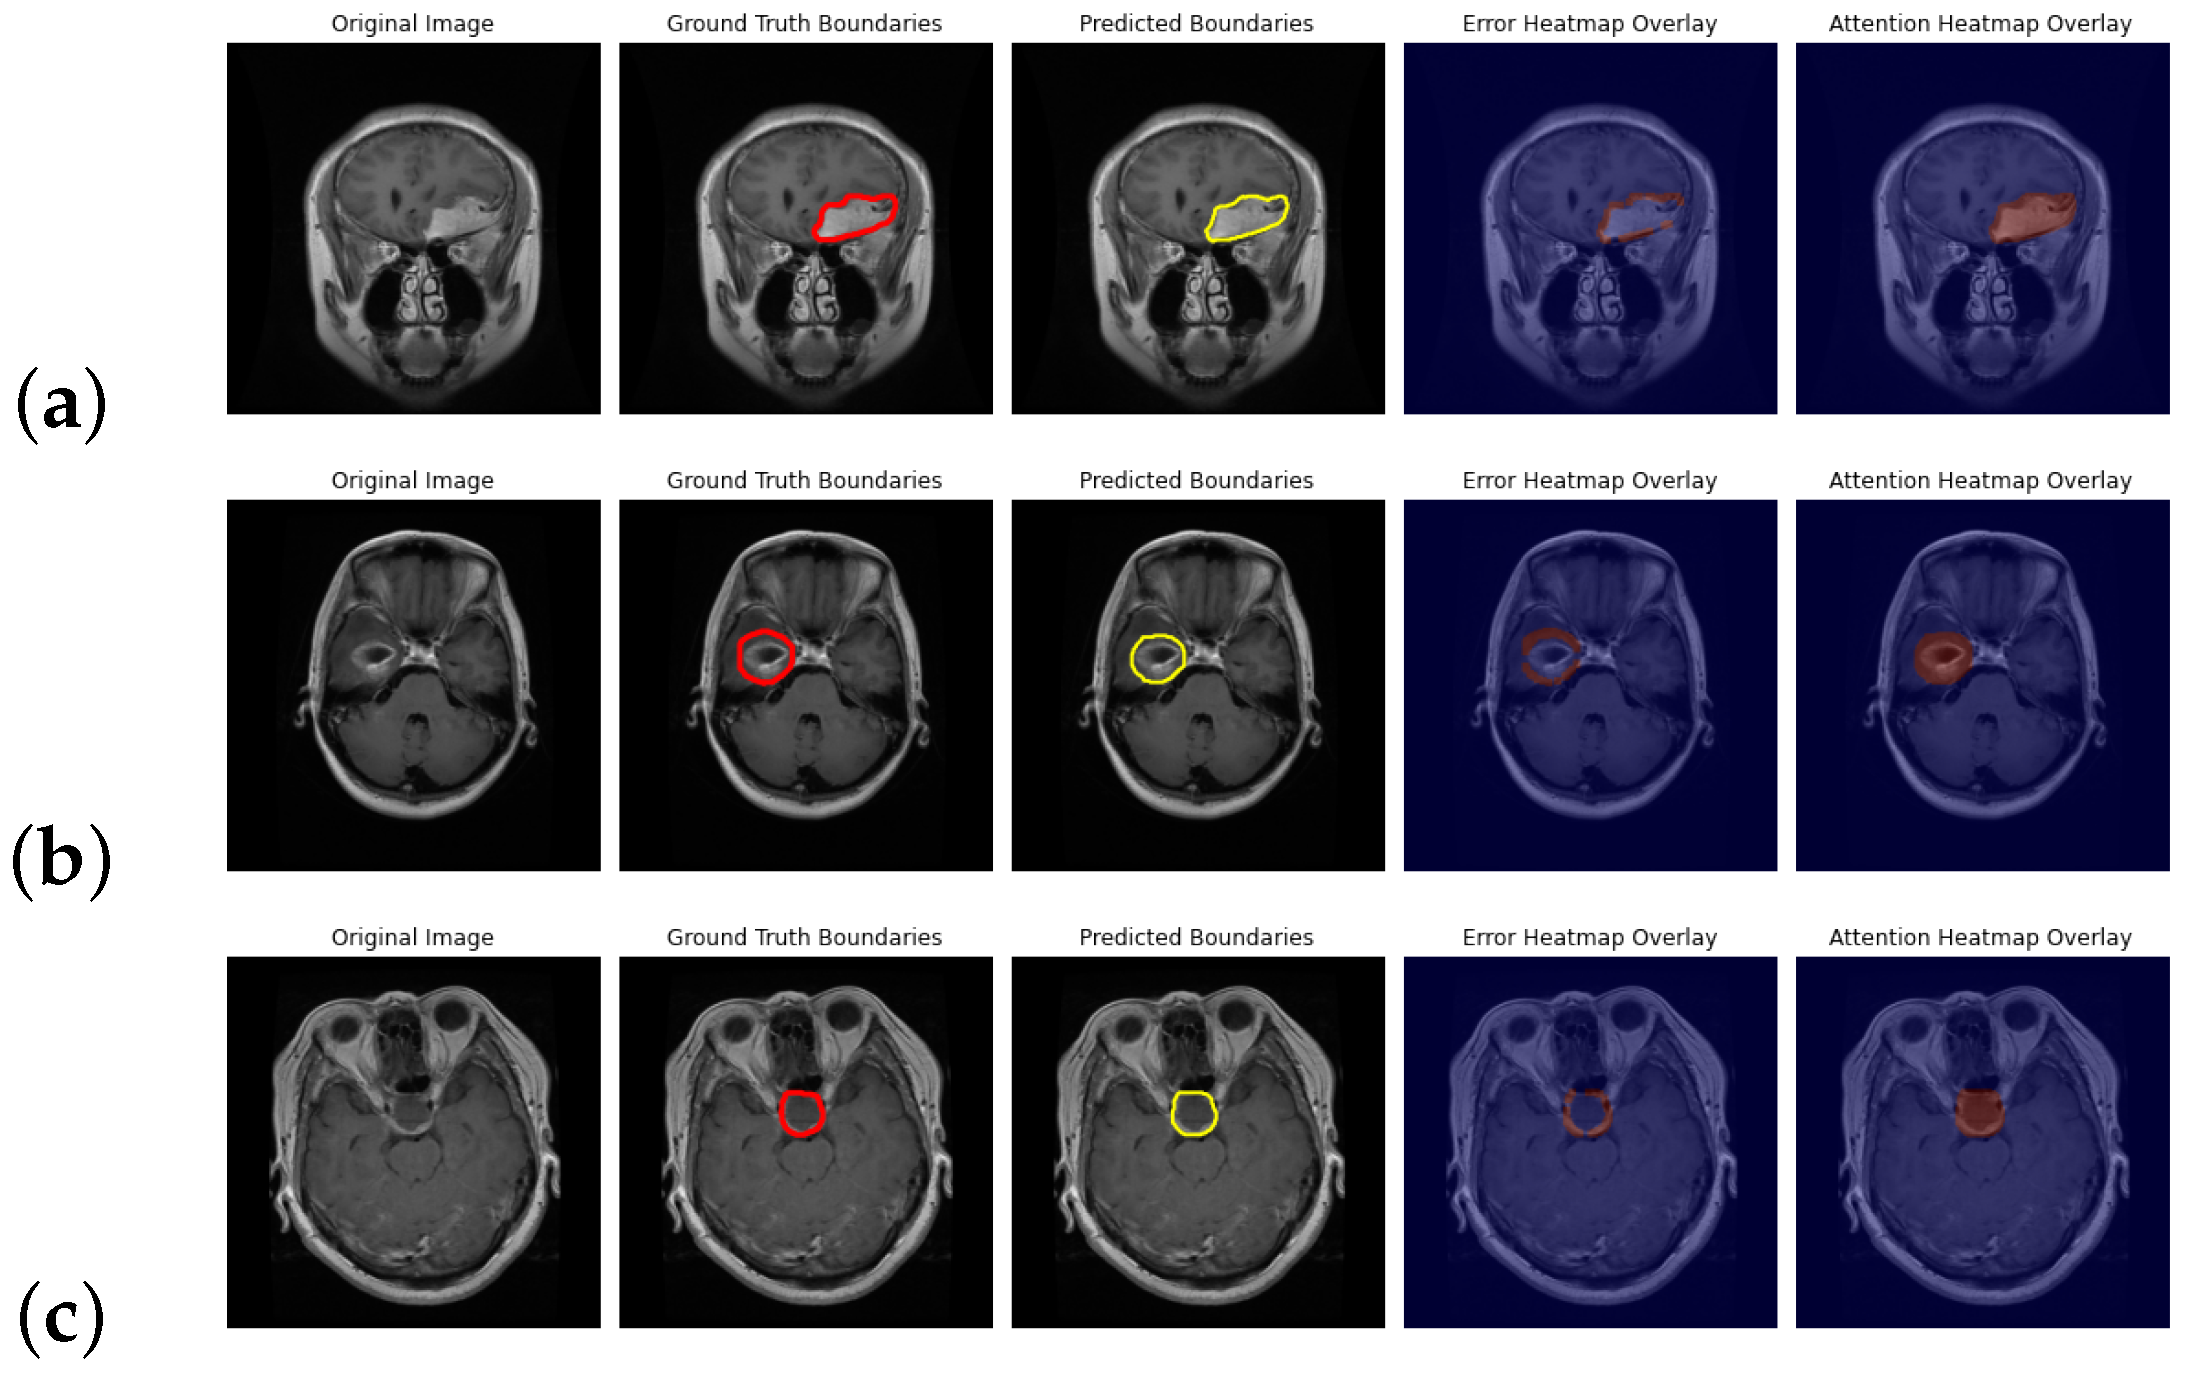

4.7. Qualitative Results on BraTS 2021: Visual and Metric-Based Analysis

4.8. Qualitative Evaluation on BraTS 2018: Visual Analysis of HGG and LGG

4.8.1. HGG: Boundary Sensitivity and Modality Reliability

4.8.2. LGG: Homogeneous Boundaries and Compact Attention Spread

4.8.3. Comparative Observations: HGG vs. LGG